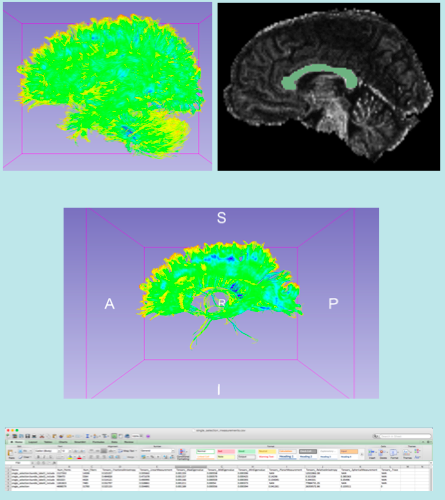

Slicer4 Diffusion Tensor Imaging Tutorial

- The Diffusion Tensor Imaging Tutorial course guides through the basics of loading Diffusion Weighted images in Slicer, estimating tensors and generating fiber tracts.

- Author: Sonia Pujol, Ph.D.

- Audience: End-users and developers

- Modules: Data, Volumes, DWI to DTI Estimation, Diffusion Tensor Scalar Measurements, Editor, Markups,Tractography Label Map Seeding, Tractography Interactive Seeding

- Based on: 3D Slicer version 4.5

- The DTI dataset contains an MR Diffusion Weighted Imaging scan of the brain.